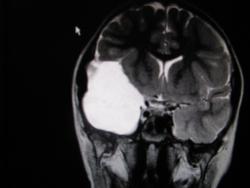

Крупная арахноидальная киста правой височной области.

Согласна, арахноидальная киста.

да, до этого мальчик жалоб не предъявлял. наверное киста увеличилась, масс-эффект на прилежащие струкутры усилился , появилась клиника.

Да, это врожденная арахноидальная киста.